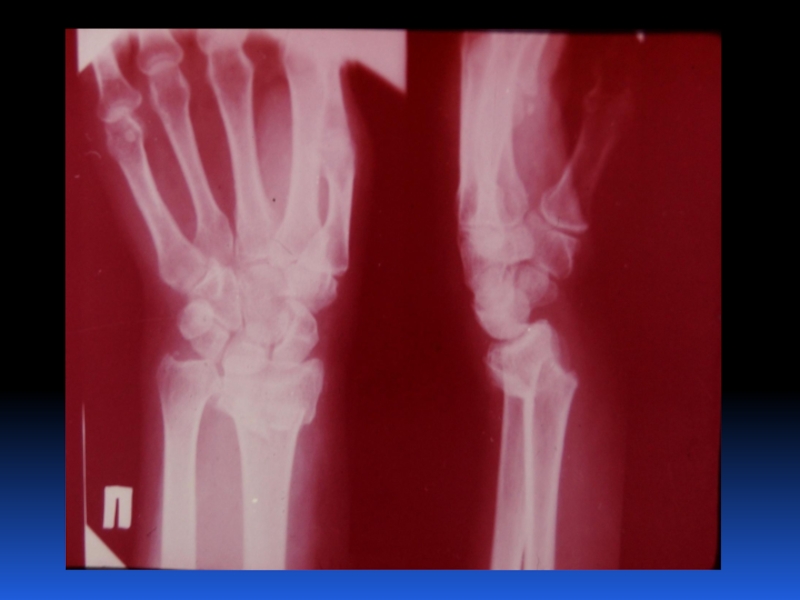

Остеопороз – это системное заболевание скелета, характеризующееся снижением костной массы и нарушением микроархитектоники костной ткани, с последующим увеличением хрупкости костей, со склонностью к патологическим переломам.

Слайд 2 Остеопороз – это системное заболевание скелета, характеризующееся снижением костной

массы и нарушением микроархитектоники костной ткани, с последующим увеличением хрупкости

костей, со склонностью к патологическим переломам.